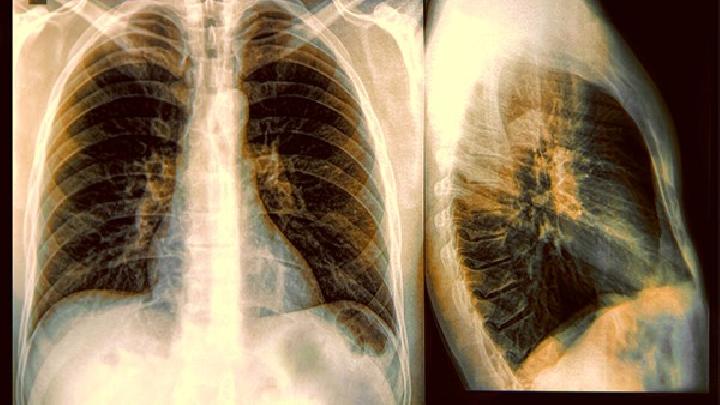

肺纤维化的发生使患者肺部肺泡的扩张和活动受限,因而气体交换量减少,易致慢性缺氧的发生,而且如果不能保证正常的通气和换气,导致进一步加重呼吸困难,需要积极开展呼吸功能锻炼。那么,肺纤维化患者进行呼吸锻炼的方法有哪些呢?